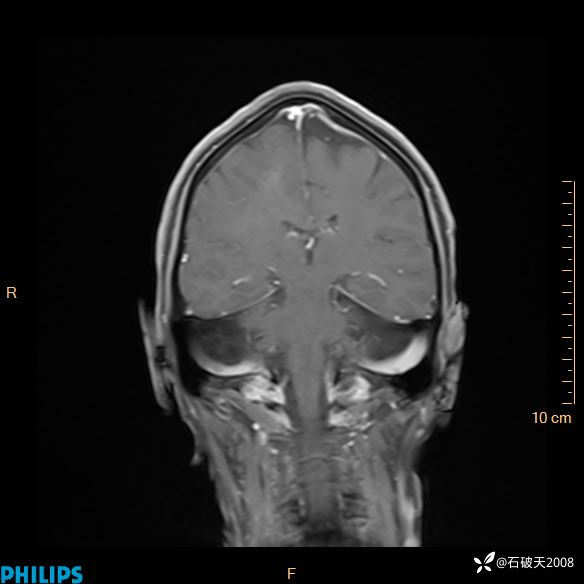

2024.2.21MR

增强冠状位